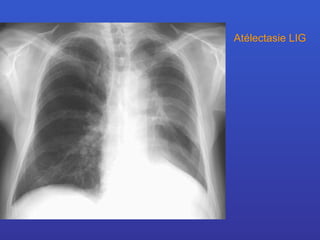

Atélectasie LIG